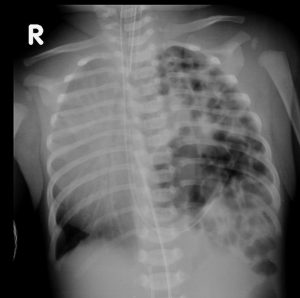

Common X-ray Findings: